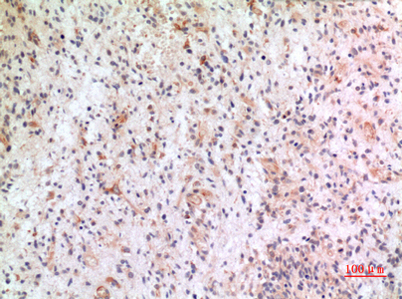

Product name: Fractalkine rabbit pAb

Dilutions: Western Blot: 1/500 - 1/2000. IHC-p: 1/100-1/300. ELISA: 1/20000. Not yet tested in other applications.

Immunogen: The antiserum was produced against synthesized peptide derived from the Internal region of human CX3CL1. AA range:231-280